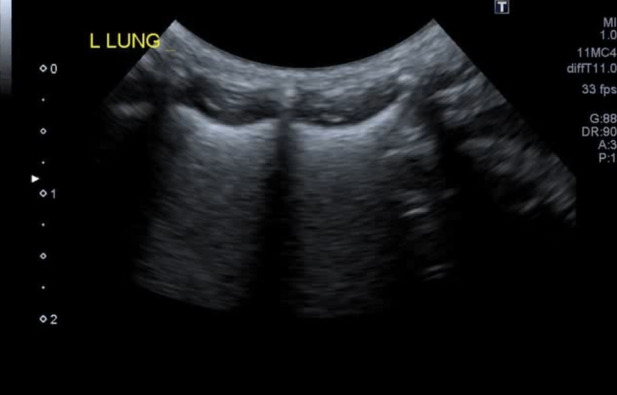

図9C 気管支肺炎の猫の肺超音波画像

雑種猫、年齢不明(中年齢以上)、避妊雌、体重3.68kg。数日呼吸の調子が悪かったが、夜から開口呼吸を認めたため来院した。肺野全域において胸膜不整と小さなConsolidationとB-lineの増数が認められた。